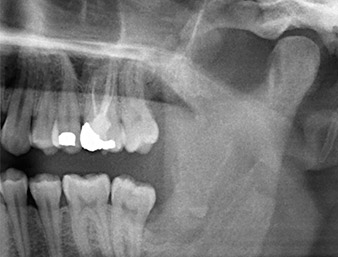

Der Wurzelrest regio 38 zeigte bereits in der Panoramaschichtaufnahme eine enge Lagebeziehung zum Nervus alveolaris inferior. (Abb. 1)